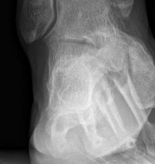

Principles of Buttress Plating

While lag screws provide excellent interfragmentary compression, they possess minimal resistance to bending and shear forces when subjected to physiological loads. Therefore, partial articular fractures subjected to axial loading (e.g., tibial plateau, distal femur, distal radius) require the application of a buttress plate.

The buttress plate functions by rigidly opposing the direction of displacement. Biomechanically, the plate must be applied to the apex of the fracture (the axilla) to effectively counteract shear forces. When the joint is loaded, the articular fragment attempts to slide along the fracture plane; the buttress plate acts as a physical barrier, converting the shear force into compressive force across the fracture site.

Image

To optimize the buttress effect, the plate is typically slightly under-contoured. When the plate is secured to the intact diaphyseal bone, the under-contouring causes the proximal portion of the plate to spring against the metaphyseal flare, actively compressing the articular fragment. Screws placed through the plate into the articular fragment are inserted in a neutralization capacity or as secondary lag screws, but the primary mechanical stability is derived from the plate's buttressing effect against the intact cortical shaft.